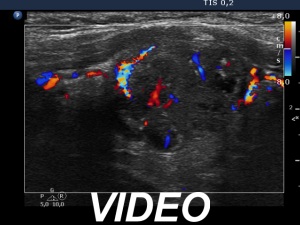

Second examination 7 years later (second row of images):

Clinical presentation. In the past 7 years, the patient had no complaints and therefore did not come to the proposed checkup either. Now he felt it was time to do an investigation.

Functional state: subclinical hypothyroidism with TSH 5.82 mIU/L, aTPO 98 U/mL.

Palpation: a hard nodule in the left lobe.

Ultrasonography. The presentation of the thyroid was essentially the same as 7 years ago. The only discrepancy was the lesion in the left lobe. Firstly, the size of the lesion have substantially increased to 25x18x25 mm (width, depth, and length, respectively), the volume was 5.89 mL which means that the volume became almost 8-times larger. Secondly, it was no more question whether the lesion was a pathological nodule or not. It turned out that this lesion is clearly a pathological nodule. Thirdly, in contrast to the former examination, the nodule has numerous microcalcifications and showed a clearly irregular, lobulated margins.

Aspiration cytology resulted in suspicion of papillary cancer.

Total thyroidectomy was performed, histopathology disclosed a T2 papillary cancer and Hashimoto's thyroiditis.